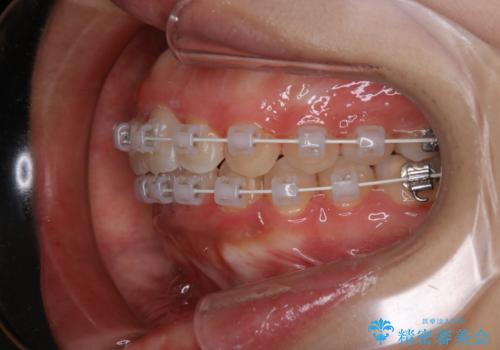

- 20代女性

- 矯正装置

- ワイヤー審美装置

- 7ヶ月

- 4年ほど前から地元の歯科医院にてインビザライン治療を行っていたが、引っ越し後に通いづらくなってしまったため、治療が途中で止まってしまっているとの事で来院されました。性格的にインビザラインの継続した使用が難しいとのことで、ワイヤー装置にて最終仕上げを行いました。

インビザラインは20時間以上の装着を厳守して頂くことで治療効果が期待できる治療となります。固定式のワイヤー装置に切り替えることで短期間で歯並びを整えることができ、大変喜んでいただけました。